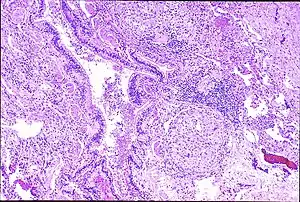

| Peribronchal non-necrotizing granuloma from berylliosis | |

Granulomas are seen in other chronic diseases, such as tuberculosis and sarcoidosis, and it can occasionally be hard to distinguish berylliosis from these disorders. However, granulomas of CBD will typically be non-caseating, i.e. not characterized by necrosis and therefore not exhibiting a cheese-like appearance grossly.[5]